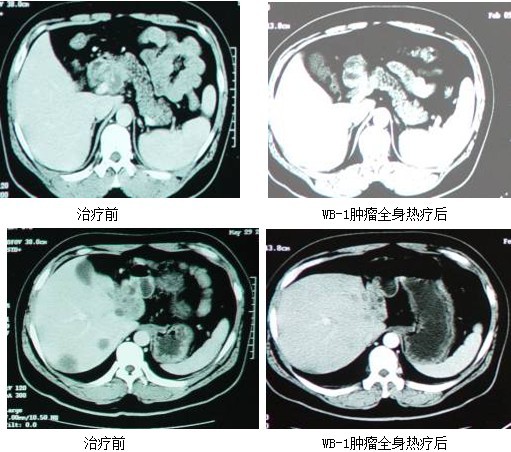

患者姓名:谭剑鸣,男,58岁,胰腺癌肝转移,广东阳江人

简要病史:诉“腰背疼痛一月”来诊,经查CT示胰头及肝内多发占位,CA199:990u/ml,临床诊断为胰腺癌肝转移。

选用GP方案(即吉西他滨+奥沙利铂)化疗,WB-1无创全身热疗前一天使用吉西他滨 ,第二天进行WB-1无创全身热疗,待开始进入39.5℃-41.5.5℃,使用奥沙利铂1.0g,10分钟内滴完。WB-1无创全身热疗后常规行第二周、第三周GP方案化疗。第一次WB-1无创全身热疗后复查CT示胰头肿瘤及肝内转移灶均缩小,CA199降低为137u/ml,后患者因故停止治疗。

三月后复查病灶又复增大,CA199再度>1000u/ml,继行两周期WB-1肿瘤全身热疗加小剂量化疗,方案同前。

治疗两月后复查,胰头部原发肿瘤完全消失,肝内仅有一大小约1cm×1cm转移灶,CA199降为300u/ml,治疗已结束半年,现患者病情稳定。